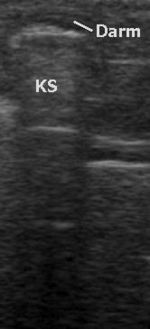

Eine aktuelle Entwicklung ist die Diagnose von Knochenbrüchen und deren Verlaufskontrolle. Insbesondere bei Brüchen im Kindesalter ist in bestimmten Regionen eine ultraschallbasierte Darstellung von Frakturen mit einer Genauigkeit möglich, die Röntgenbilder überflüssig machen kann. Zum gegenwärtigen Zeitpunkt ist der Einsatz dieser Fraktursonografie bei handgelenksnahen Unterarmfrakturen, Ellenbogen- und Oberarmbrüchen möglich.

Alle wasserhaltigen, blutreichen Organe sind für den Ultraschall gut untersuchbar. Schlecht untersuchbar sind alle gashaltigen oder von Knochen bedeckten Organe, zum Beispiel der Darm bei Blähungen, die Lunge, Gehirn und das Knochenmark. Manche Organe sind im Normalzustand nur schwierig, im krankhaft vergrößerten Zustand dagegen gut erkennbar (Blinddarm, Harnleiter, Nebennieren).

Das Verfahren hat in tief gelegenen Geweben eine geringere Raumauflösung als die CT und MRT. Auch die Weichteil- Kontrastauflösung kann der bei der MRT unterlegen sein. Gas und Knochen verhindern die Ausbreitung der Ultraschallwellen. Daher ist die Sonografie bei gasgefüllten Organen (Lunge, Darm) und unter Knochen (Schädel, Rückenmark) erschwert. Anders als bei anderen bildgebenden Verfahren gibt es keine standardisierte Ausbildung. Daher bestehen große qualitative Unterschiede in den diagnostischen Fähigkeiten der Anwender.